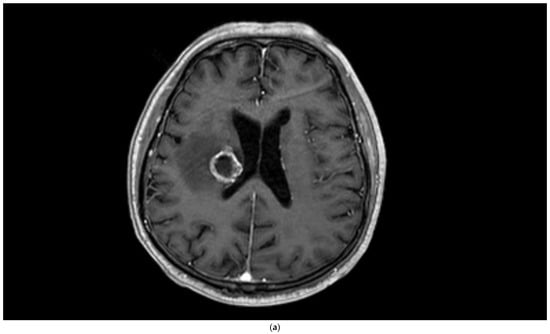

Figure 2.

Brain magnetic resonance imaging (MRI) of a 67-year-old male with small-cell lung carcinoma revealed (a) peripherally enhanced right periventricular mass on post-contrast axial T1-weighted image and (b) hyperperfusion with a rCBV of 2.4 in perfusion-weighted imaging. Pink ROI is from metastatic nodule and white ROI is from contralateral parenchyma.